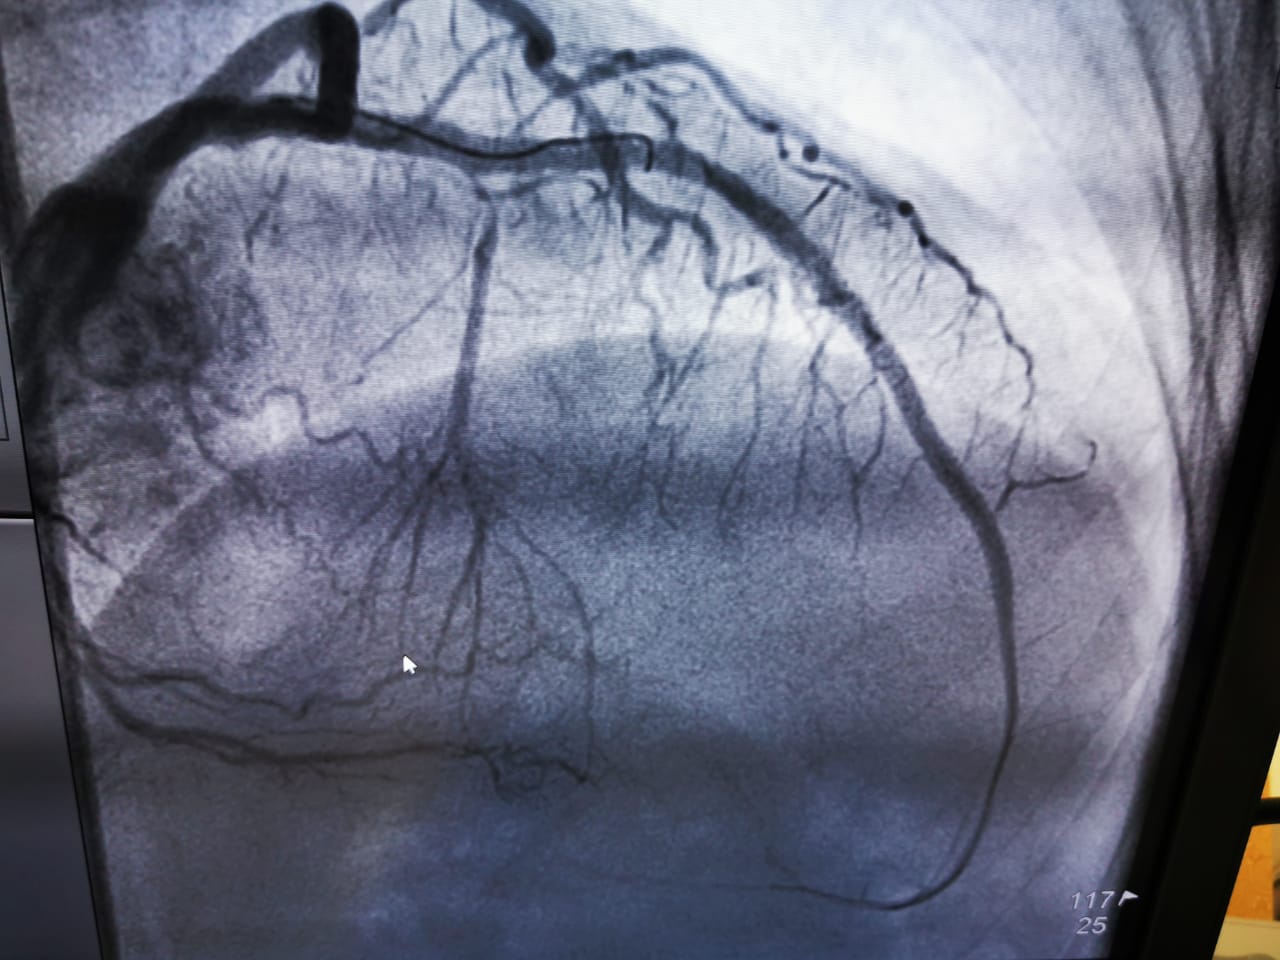

It gives us immense pleasure to have witnessed India’s First laser atherectomy (Lad uncrossable with balloon, Laser 0.9 and 1.4 ELCA) at JNM hospital Raipur chattisgargh with Dr Smit Srivastava, proctored by Dr. Arun Kalyanasundaram. We thank everyone who participated in this event and made it possible!